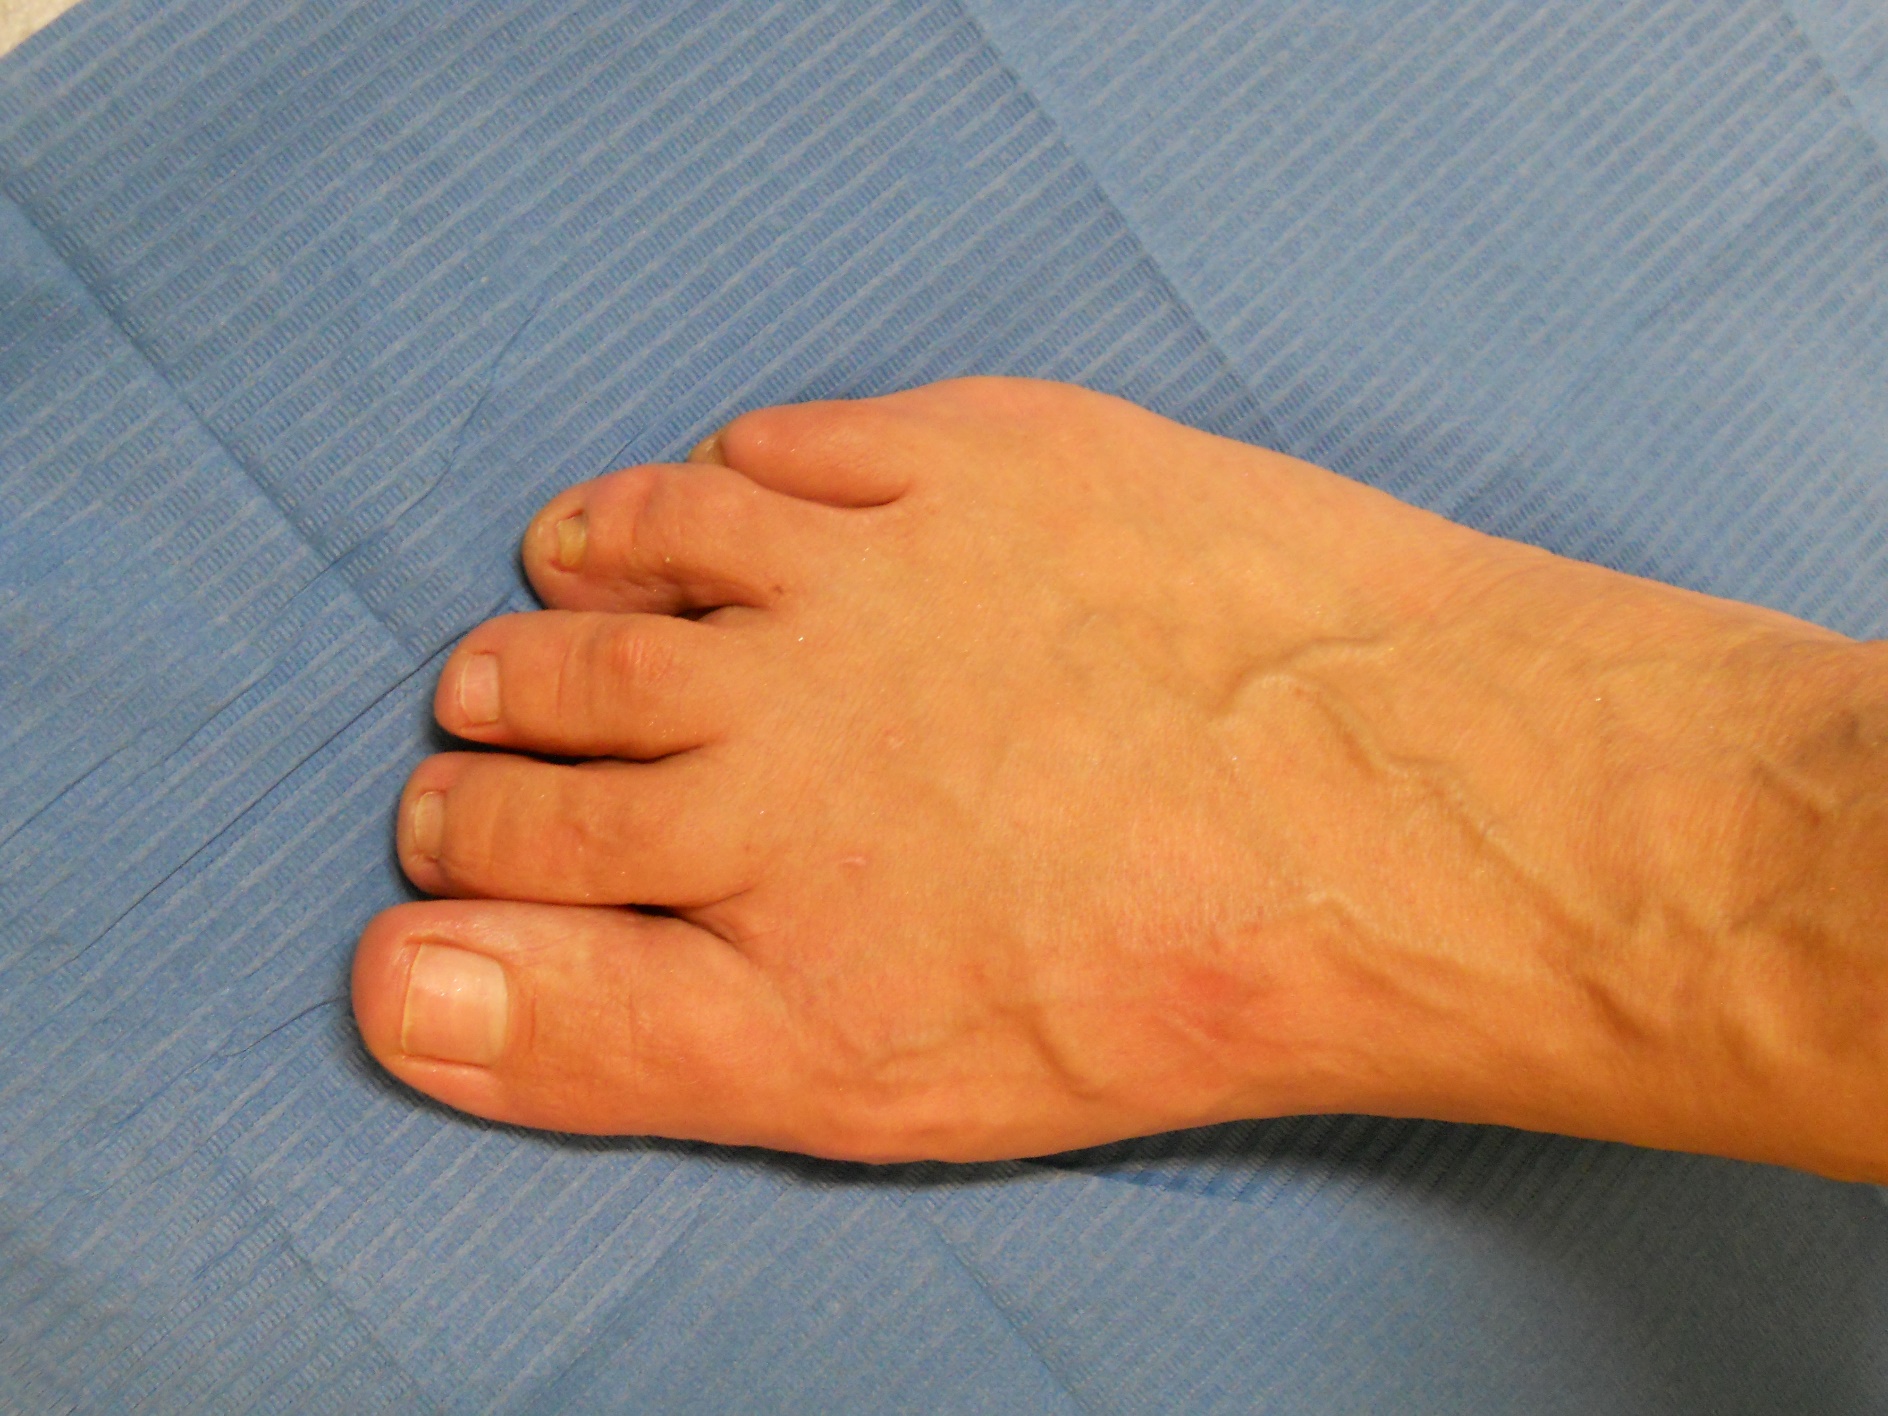

Dedos en garra

Dedos en garra: antes Dedos en garra: después